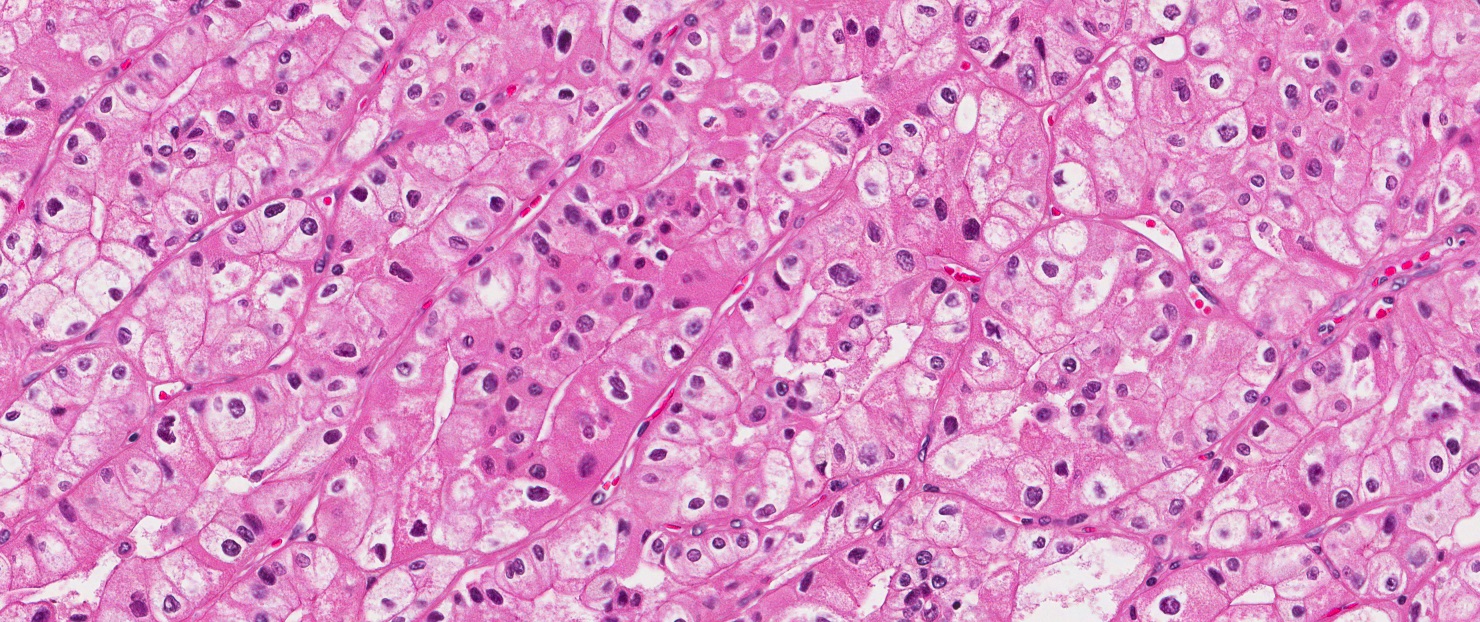

腎細胞がんが原因となる 90%すべての腎臓がんの中で最も多い。がん細胞が腎臓の尿細管で形成されると発生します。尿細管は腎臓にある小さな管で、尿を作るために血液から老廃物をろ過するのに役立ちます。

• 生検では、針を使用して腫瘍の可能性がある場所から組織サンプルを採取します。